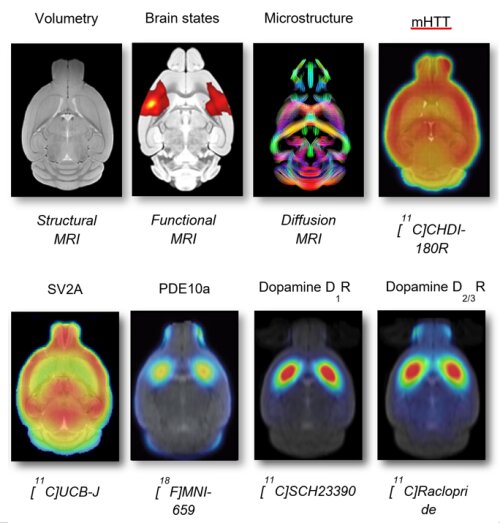

Picture description: Example of a combined multi-modal platform of PET and MRI biomarkers for the rodent (mouse) brain, as published by our research team: Adhikari et al., Sci Rep, 2023; Vasilkovska et al., Neurobiol Dis, 2023; Bertoglio et al., Science Transl Med, 2022; Bertoglio et J Nucl Med, 2022; Bertoglio et al., Mol Neurobiol, 2020; Bertoglio et al., J Nucl Med, 2018; Bertoglio et al., Mol Imaging Biol, 2021; Bertoglio et al., Plos One 2018; …

Figure Description: This figure highlights the pathologies of our own academic interest. The biomarker platform can be applied in a broader range of diseases.